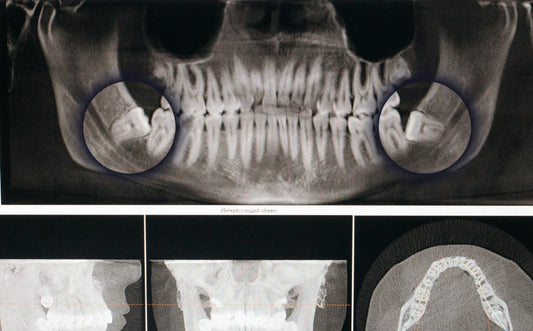

Weisheitszähne entfernen: Alles, was du über die OP, die Schmerzen und die Genesung wissen solltest

Weisheitszähne entfernen: Alles, was du über di...

Wild Origins

Hast du auch dieses mulmige Gefühl, wenn dein Zahnarzt plötzlich sagt: „Wir sollten uns mal Ihre Weisheitszähne anschauen“? Du nickst nur, während dir im Kopf das Wort "Operation" aufblinkt und...